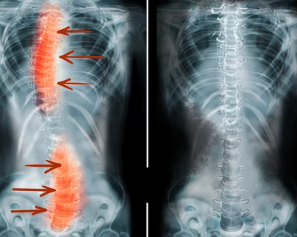

3. 척추 측만증의 진단 방법

병원을 방문하여 다음과 같은 전문적인 검사를 받을 수 있습니다.

- X-ray 검사: 척추의 휘어진 정도를 확인